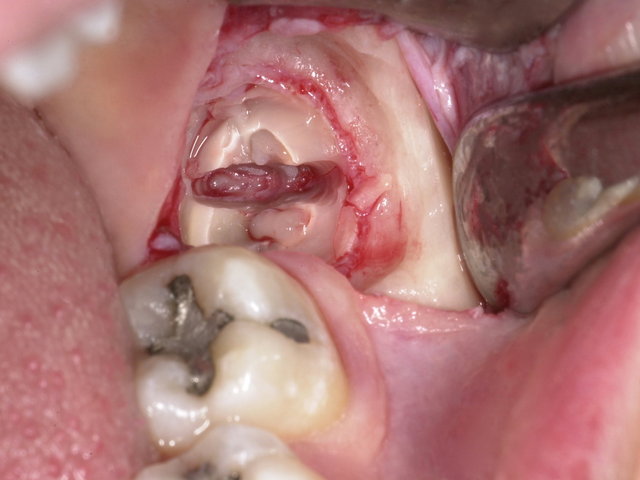

Operative Weisheitszahn-Entfernung ...

Operative Weisheitszahn-Entfernung ... ✓